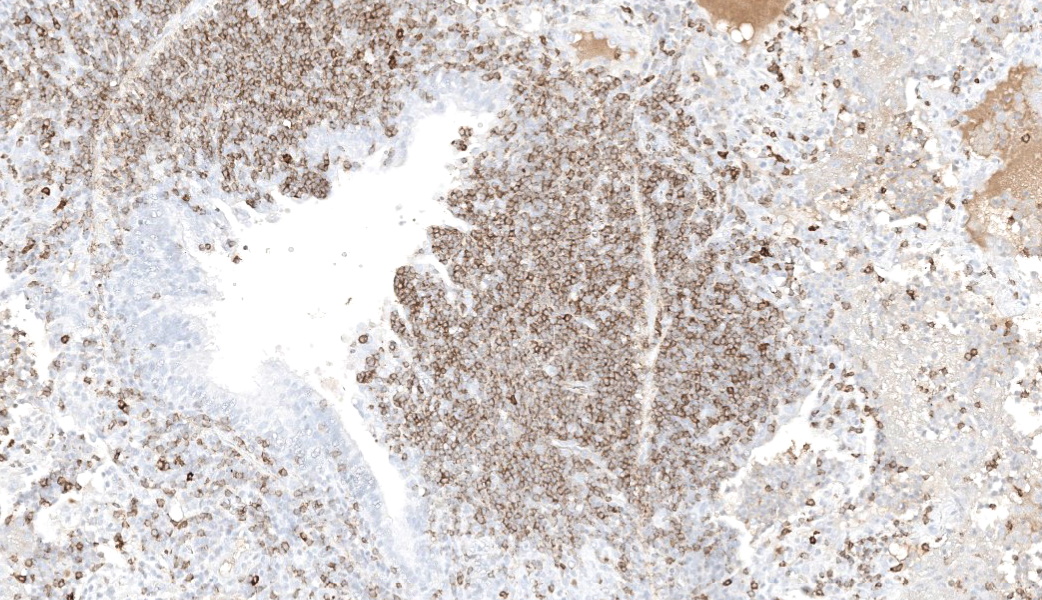

Immunohistochemical markers

|

Marker |

Cell type |

Tissue |

Number of positive cells |

Positive cell distribution |

CD79b |

B Cell |

Lung |

+++ |

Majority of cells within neoplastic infiltrate, scattered cells within peribronchial and peribronchiolar spaces, interlobular and alveolar septae and alveolar lumen |

Lymph node |

The majority of cells within the cortex and moderate numbers (30-50% of cells) within the medulla |

||

Spleen |

Majority of cells within red and white pulp |

CD3 |

T Cell |

+ |

Scattered throughout parenchyma, and small numbers accompanying neoplastic infiltrate |

++ |

Moderate numbers multifocally throughout the medulla |

Predominantly around blood vessels |

In this case, neoplastic cells were also found in the liver, spleen and heart of the camel. No neoplastic cells were found in the kidneys or in two sections of bone marrow (rib and sternum). The presence of atypical lymphocytes within the peripheral blood collected at the initial clinical examination greatly aided the diagnosis of lymphoma or leukemia in this case (Figure 1) and allowed the clinician to understand why this animal did not improve like the others in the herd once nutrition was improved. The neoplastic cells observed in the peripheral blood was suspected to be secondary to the lymphoma, given that no neoplastic cells were found within the bone marrow of the bones examined histopathologically. Leukemia is a feature of less than 20% of lymphomas in animals and is more commonly a feature of T-cell lymphomas.9 Leukemia is most likely observed when the lymphoma invades the bone marrow or spleen, the latter of which contained neoplastic cells in this case.9 In this case a B-cell phenotype was confirmed via immunohistochemistry (Figures 7-11).There are only a few reports in the literature describing lymphoma in dromedary camels. Similar to this case, the disease is typically reported in adult animals (>7 years) and has been reported in both male and female camels. Common clinical presentations include weight loss, anorexia, polyuria and polydipsia, with one report also describing peripheral lymphadenopathy and bilateral masses in the conjunctiva of one animal.3,4,6 Peripheral lymphocytosis, sometimes with significant atypia in circulating lymphocytes and lymphoblasts, has been reported occasionally but is not always a feature of the disease in dromedary camls.3,7

In contrast to this case, all cases in the literature from dromedary camels were identified as T-cell lymphomas. In those cases, lymphocyte lineage identification was performed using immunohistochemistry and identified the neoplastic cells as CD3 (pan T-cell) positive and either CD20 or CD79a (pan B-cell markers) negative.3,4 More recently, flow cytometry has been used to further classify a multicentric T-cell lymphoma as a gd T-cell lymphoma and a combination of CD4 and WC-1 markers.4 Other markers which have been used in the literature to differentiate round cell neoplasms in camelids include PAX-5, CD79b (B-cell markers), CD5 (T-cell marker), MUM1 (plasma cell marker), CD18 and CD68 (histiocyte markers).1,4,6,8